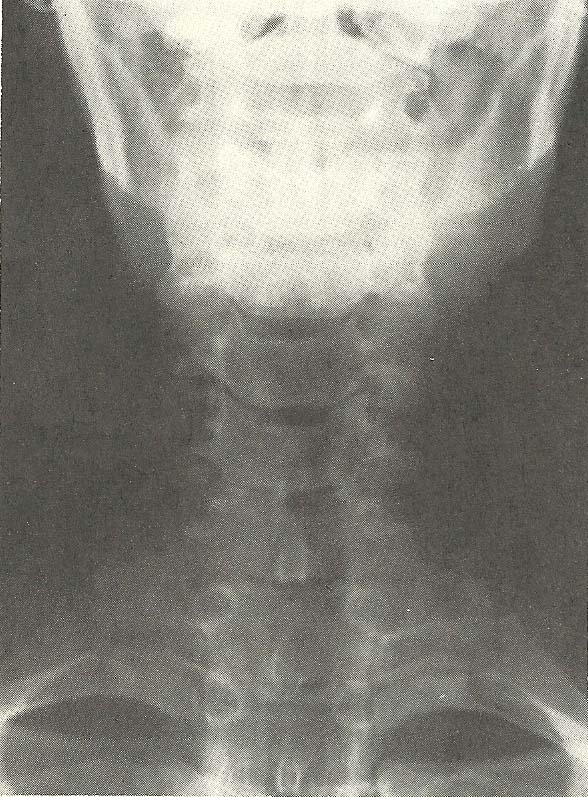

Case Illustrating Classifications A-1, A-3, A-4, A-8, and A-9

The x-ray views presented next are those of a 69-year-old female (Figs.

6.60--6.62). There is foraminal narrowing at four levels on the right and two

on the left due to proliferative changes (A-9). Flexion subluxation exists at

C4 (A-1), and marked interspace narrowing is found at C5, C6, and C7 (A-8). A

loss of normal cervical lordosis is evident. Rotary subluxation is present at

C2 and C3 (A-4). Also note the generalized osteoporosis.

This lady complained of objective vertigo, tinnitus, and suboccipital pain

and pressure. She had consulted her family physician 2 weeks previously, at

which time she received an ECG, chest x-ray, and several blood tests. She was

informed that nothing serious was wrong and her symptoms were related to a

"weak chest."

Chiropractic examination revealed the following pertinent information:

(1) blood pressure, 190/110;

(2) pulse, 108;

(3) height, 5 feet 5 inches;

(4) weight, 123 lbs;

(5) cicatrix formation of the left tympanic membrane due to an old rupture;

(6) postnasal drip with hyperemia of the posterior pharynx;

(7) on auscultation, slight accentuation of the aortic sound; and

(8) the ranges of cervical motions showed restricted flexion and extension as well as in right lateral flexion; and

(9) a cervical compression test was positive bilaterally.

A working diagnosis of hypertension, possibly of neurogenic origin, was

made. The patient was placed on a program of conservative chiropractic care,

and after a month her blood pressure had stabilized in a range between 140/80

and 150/80. At the same time, her vertigo, tinnitus, and suboccipital pain

were eliminated, and the ranges of cervical motions were increased. She was

placed on supportive treatment at this time.